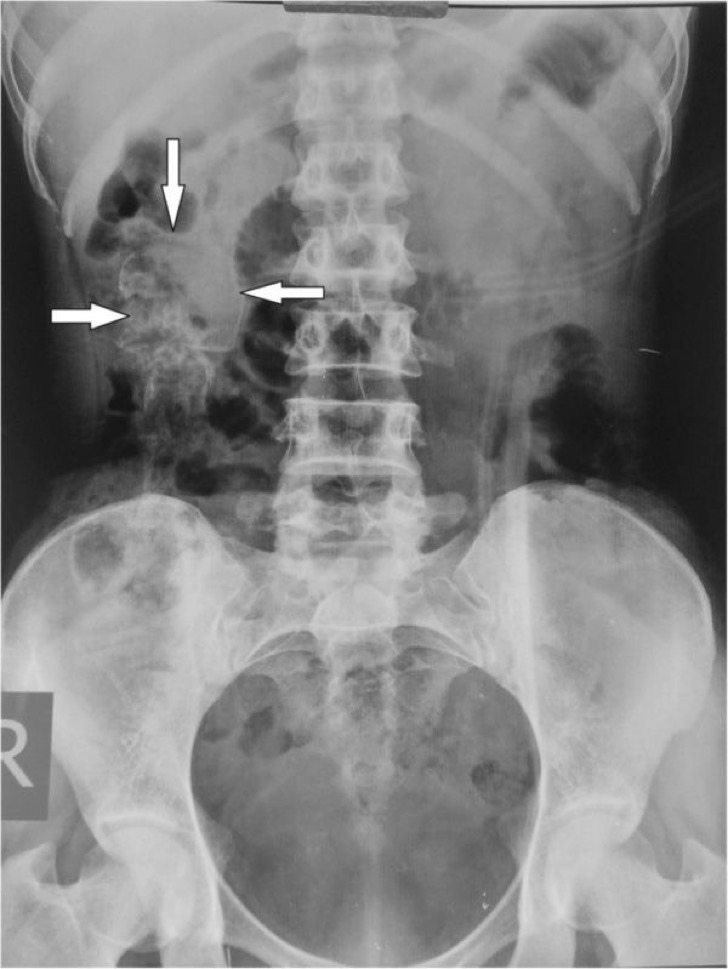

Ecografiile și examinările amănunțite au semnalat un amănunt șocant în pântecele ei era un făt complet pietrificat... de 30 de ani.

Până după 30 de ani, când din abdomen i-a fost extirpat un făt pietrificat.

În acele vremuri, puțini auziseră de boala numită Litopiedion sau ”Bebelușul de Piatră”, un fenomen foarte rar (1.3-3% din sarcinile abdominale avansate) care apare atunci cand un fetus moare in timpul unei sarcini ectopice (implantarea embrionului in orice alt tesut in afara de cel al peretelui uterin).

El este prea mare pentru a fi resorbit de catre corpul matern, ramane in cavitatea abdominala si incepe sa se calcifieze subcutanat (proces ce apara mama de tesutul mort si previne infectia).

Pentru că nu există simptome, fătul nu este detectat. De multe ori, el se confundă cu tumoarea ovariană.